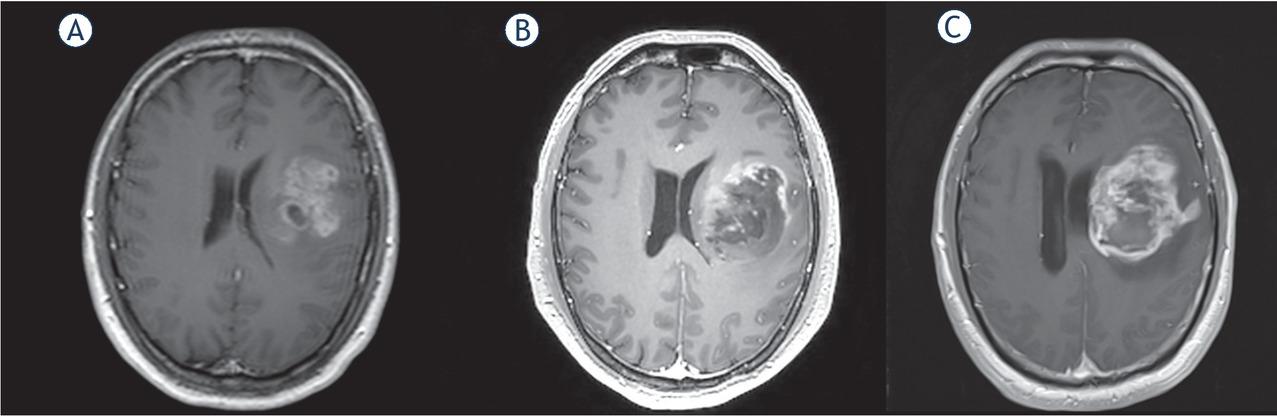

A 37 y.o. male patient, after an episode of dysarthria, underwent a neuroradiological workout. MRI images showed a left fronto-parieto-insular enhancing lesion suspicious for ex novo GBM. FLAIR and EN MTD were respectively 56.59 mm and 42.02 mm. After a week, he repeated the MRI with spectroscopy showing elevation of Cho and reduction of NAA values, elevation of Cho/NAA ratio, mild elevation of lactate signal. At the same time, central necrosis was visible. A diagnosis of GBM was made. FLAIR and EN MTD were 59.83 cc and 48 cc respectively. VDE was 169.23 mm/year for FLAIR tumor volume, whilst for EN was 311.81 mm/year. Due to poor neurological condition and tumor location, surgery was avoided. Following further neurological deterioration, he underwent a new MRI scan 2 weeks later. FLAIR tumor MTD was 72.60 mm, EN MTD was 52.16 mm. At this point, chemotherapy with temozolmide (TMZ) started. About two months later, a repeat MRI study showed good response. MTD was 67.37 mm for FLAIR tumor volume and 43.80 mm for EN, in which TMZ effect was higher (Figure 1). In fact, ΔMTD was - 5.22 mm and - 9.36 on FLAIR and EN nodule volume, respectively. Values of ΔMTD, VDE and Acc calculated according to equations [2], [4,] [5], [6], [7] for every MRI scan are listed in Table 1, divided for FLAIR and EN volumes. 6 months after initial diagnosis the patient remains alive.

MRI scans in Patient 2 at 0 (A), 18 (B) and 54 (C) days. (T1 with gadolinium sequences).